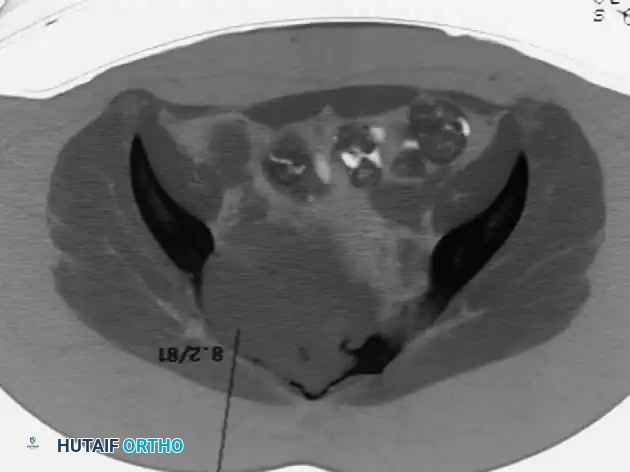

Management of Axial and Inoperable Lesions

When epiphyseal-type tumors arise in the axial skeleton, such as the sacrum, surgical morbidity increases exponentially. Resection of sacral lesions can result in massive hemorrhage, loss of bowel/bladder control, and severe spinopelvic instability.

For large, destructive lesions in the sacrum (as seen in aggressive GCTs or rare axial chondroblastomas), CT-guided core needle biopsy is mandatory to confirm the diagnosis. If the morbidity of surgical extirpation is deemed unacceptably high, patients are referred for definitive radiation therapy. Serial arterial embolization may also be employed to reduce tumor volume and alleviate pain.